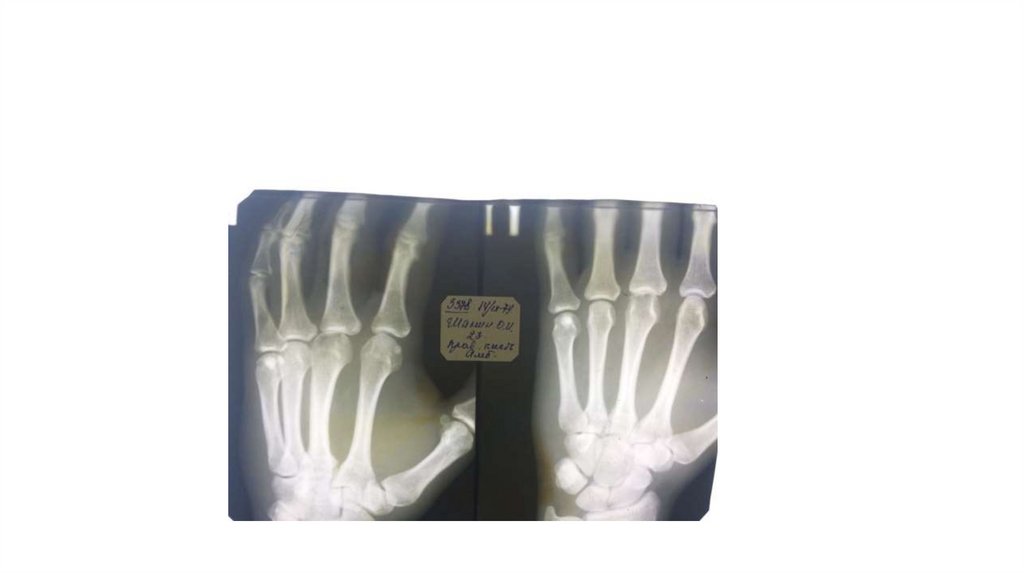

Воспалительные заболевания опорнодвигательного аппарата

«Воспалительные

заболевания опорнодвигательного аппарата»